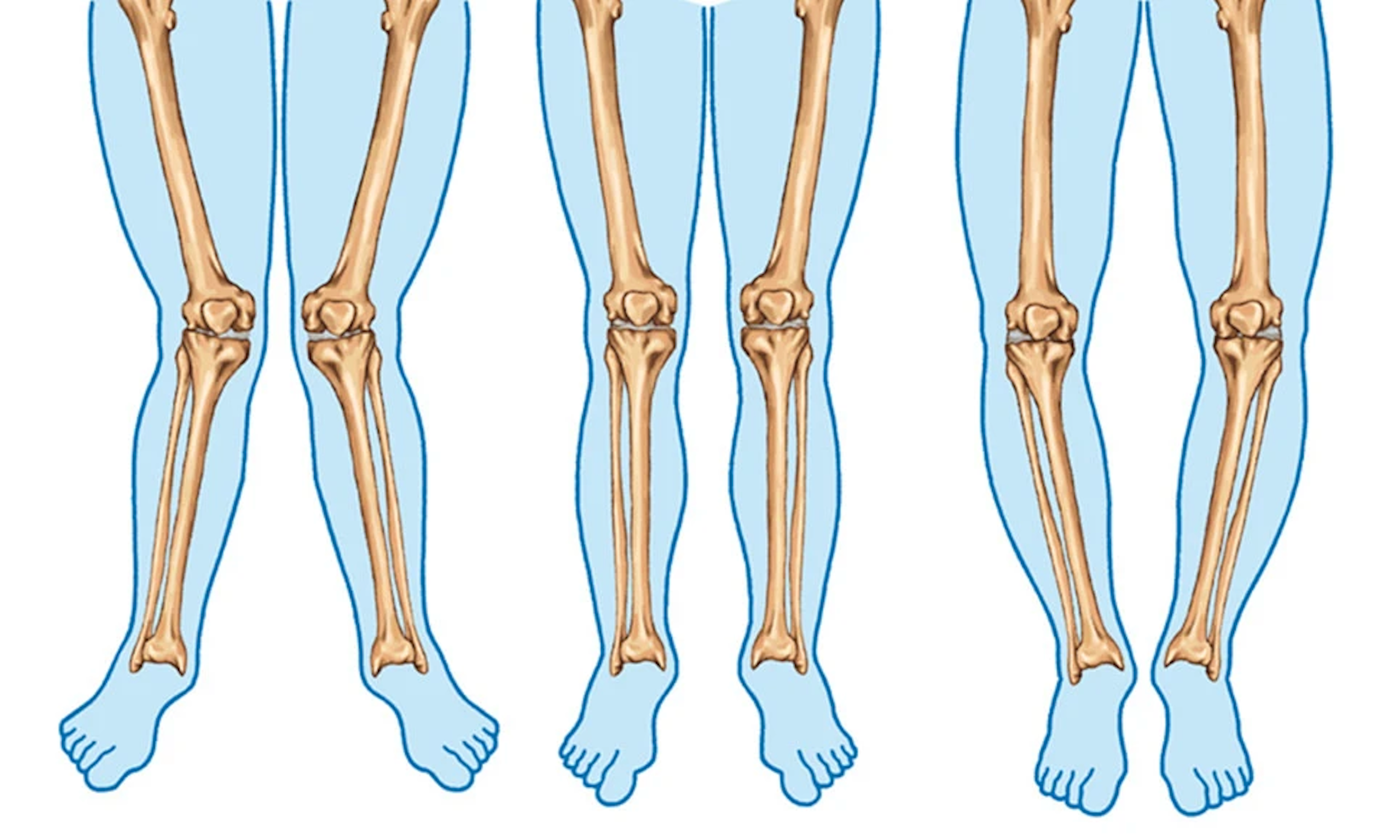

Diz eklemini oluşturan kemiklerin dizilimi bozulduğunda osteoartrit gelişebilir. Dizilim bozukluğu dizin iç veya dış tarafına ekstra baskı uygulayabilir. Zamanla bu ekstra baskı, eklem kıkırdağını aşındırarak dizde ağrı ve sertliğe neden olabilir.

A.Varus diz görünümü

C. Kemik kama çıkarılması ve dizilimin düzeltilmesi